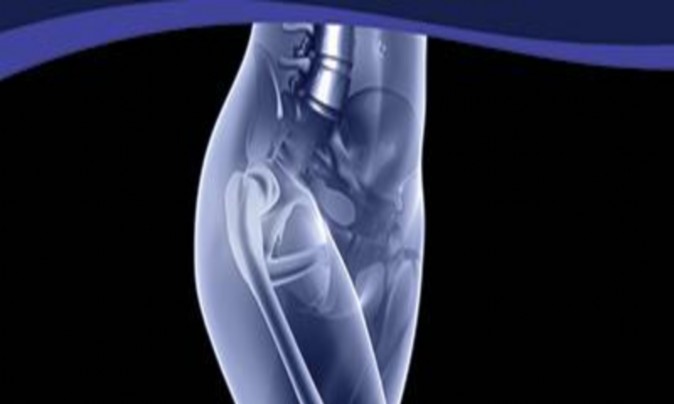

ORTHOPEDIC MCQS ONLINE OB 20 2B RECONSTRUCTION 156) A 66-year-old male undergoes the procedure shown in figur…